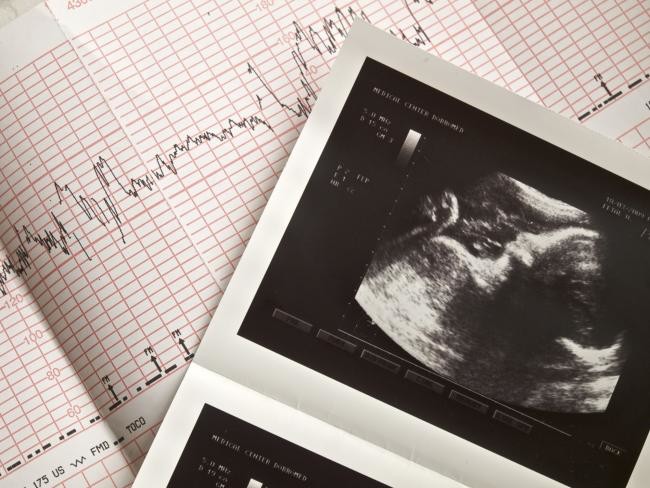

Mediante la monitorización gráfica del latido cardiaco del bebé y de la actividad uterina de la embarazada (se registran los movimientos fetales), se comprueba que el bebé está bien. Se trata de una prueba indolora que se realiza en los hospitales o clínicas ginecológicas, normalmente a partir de la semana 38 o 39 y hasta el momento del parto, que es cuando la salud del feto puede comprometerse.

La monitorización comprobará que el funcionamiento placentario y la oxigenación fetal son adecuados y además si lo realiza el ginecólogo se suele aprovechar para hacer una ecografía y/o un examen de la madurez del cuello uterino, el estado de borramiento del cuello del útero.

En este tiempo se va grabando un gráfico que anota todos los datos gracias a los cables que unen los traductores a los monitores, las pantallas donde también podremos ver la actividad. En algunas ocasiones, nos piden que pulsemos un botón conectado al monitor cada vez que notemos que el bebé se mueve.

El bienestar fetal puede ir indicado por una frecuencia cardiaca de entre 120 y 160 latidos por minuto y aparecen cinco o más movimientos del bebé en esa media hora que dura la monitorización. Los movimientos se aprecian también por el aumento momentáneo de frecuencia cardiaca.